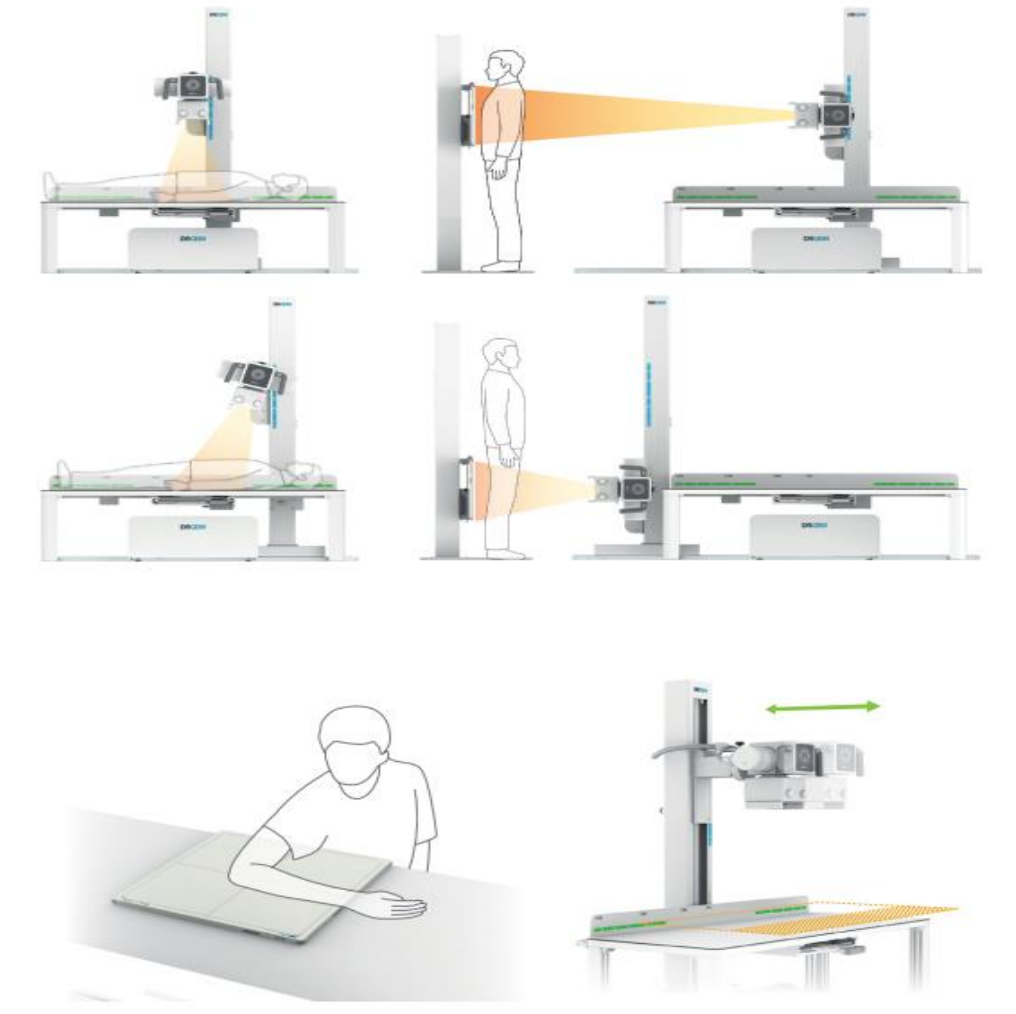

Широкие возможности позиционирования

эргономике, все механические перемещения стойки доступны с полным контролем параметров экспозиции и фокусного расстояния, а так же углов положения излучателя к пациенту и цифровому приемнику.